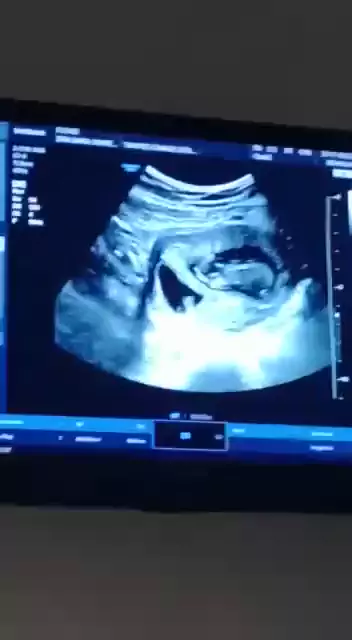

estava grávida de gêmeos placenta separada mais perdi um com 7 semanas.